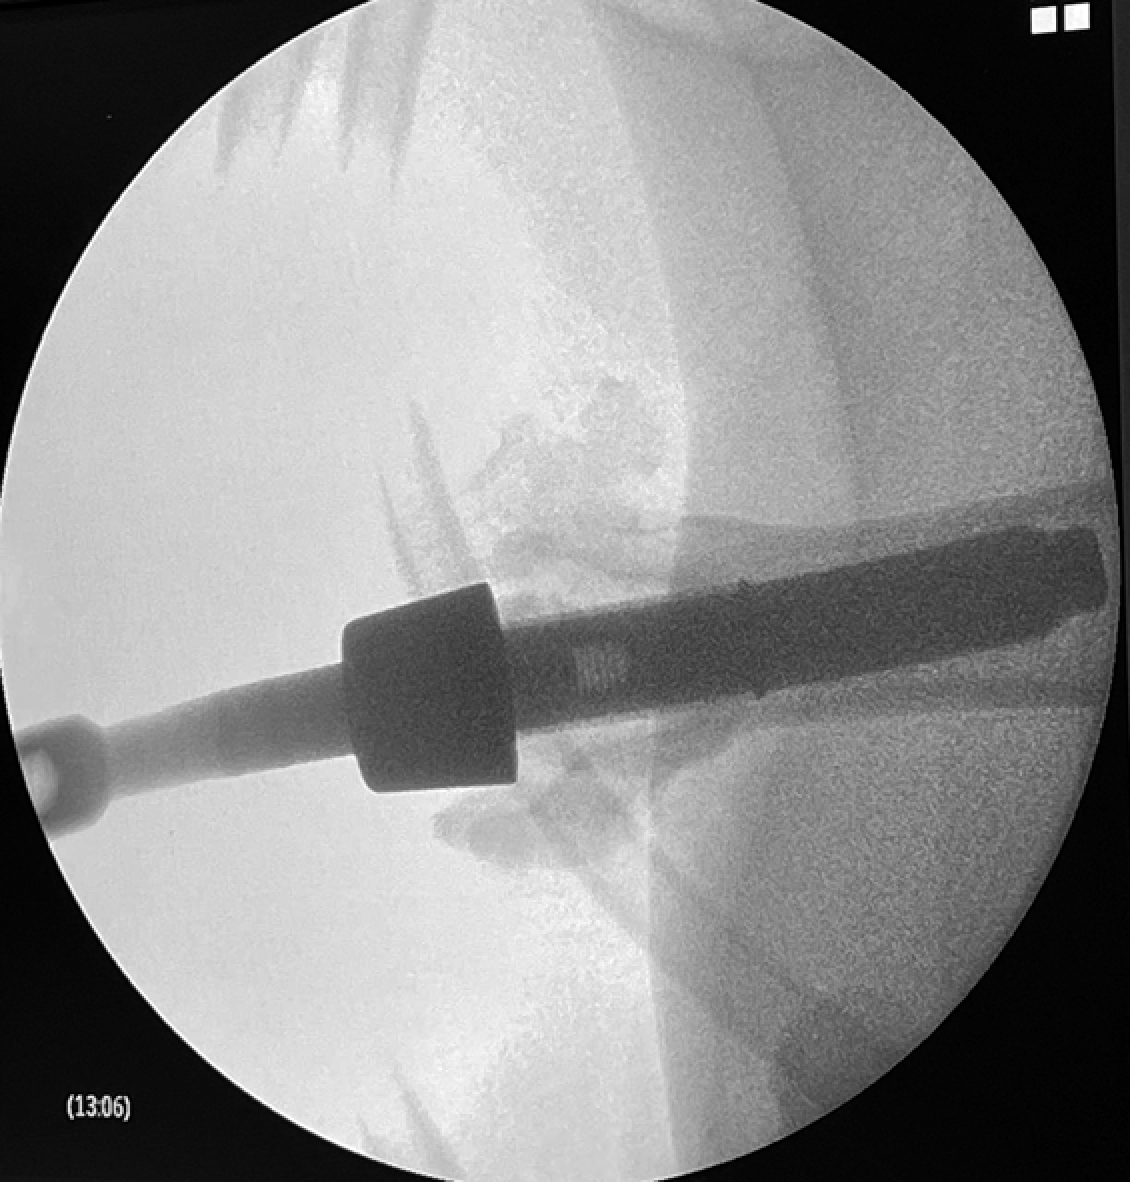

За 30 мин. до начала операции с целью профилактики инфекционных осложнений внутримышечно животному был введен антибиотик широкого спектра действия. После стандартной асептической подготовки операционного поля (выбривание шерсти на правой задней конечности, многократная обработка растворами антисептиков, изоляция стерильным операционным бельем) была выполнена ампутация правой задней конечности на уровне средней трети бедренной кости. Крупные сосуды и нервы были тщательно лигированы. После остеотомии бедренной кости был вскрыт костномозговой канал. Канал последовательно рассверливался набором стерильных хирургических сверл возрастающего диаметра (11, 12 и 13 мм). Интрамедуллярная часть имплантата (диаметр интрамедуллярной части 13,5 мм) была установлена в подготовленный костномозговой канал под контролем электронно-оптического преобразователя (С-дуги). Мышцы культи были ушиты над проксимальной частью имплантата для создания мышечной муфты. Кожная рана ушивалась послойно с оставлением активного дренажа. Была проведена интраоперационная антисептикопрофилактика (рис. 3).

Рисунок 3. Результат первого этапа операции: a — сформированная культя; b — рентгенограмма имплантированного интрамедуллярного компонента